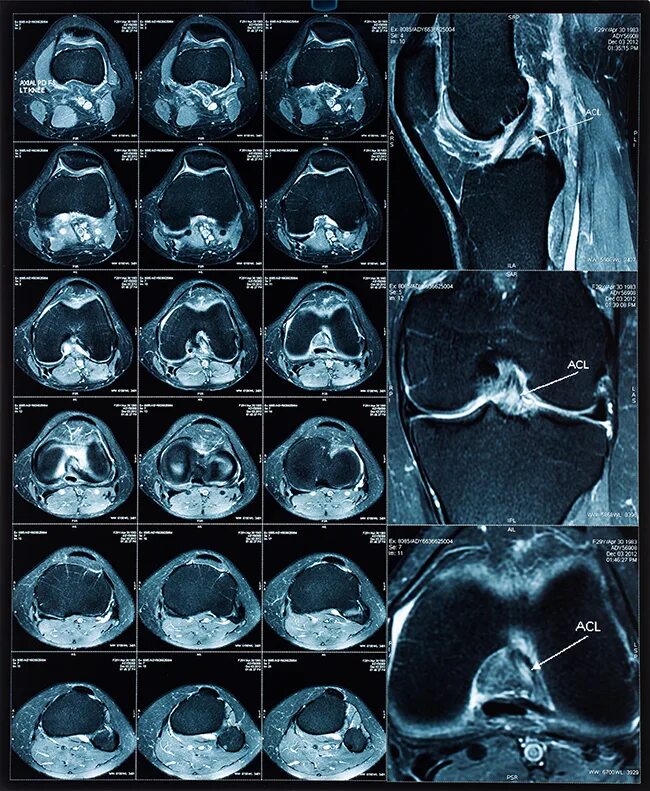

Гонартроз мрт